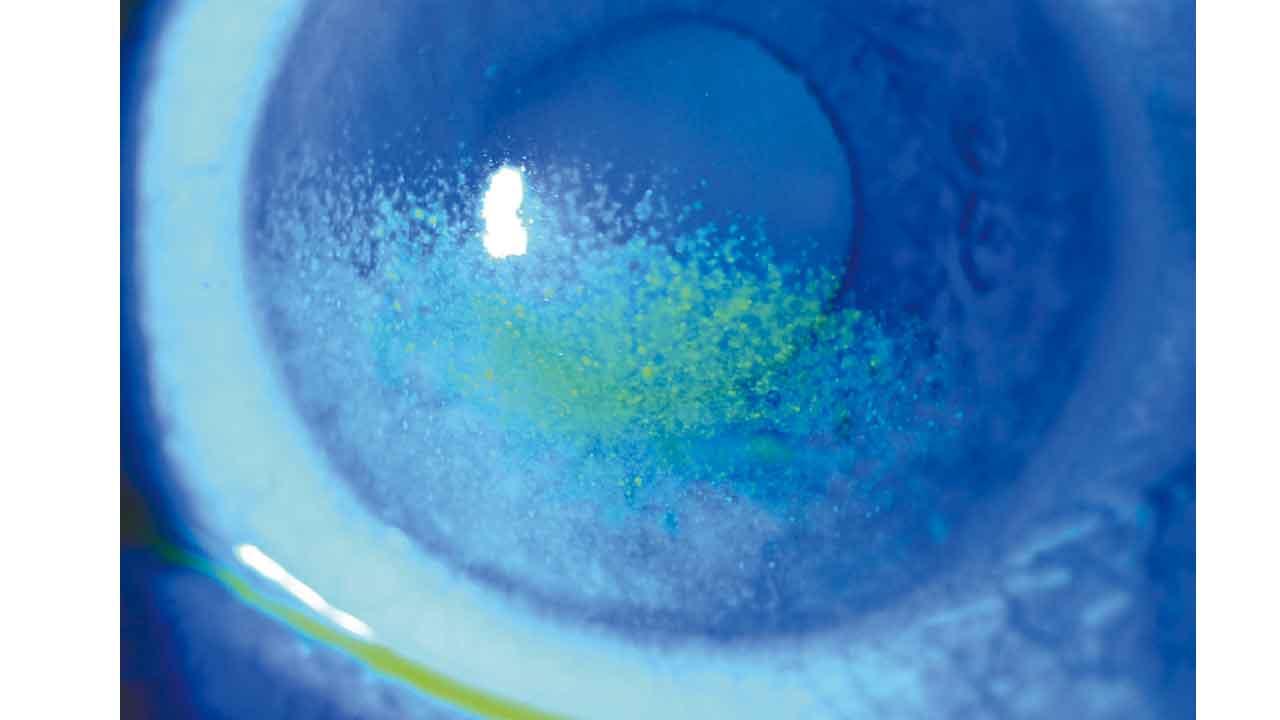

透過螢光劑藥水和藍光檢查,X眼睛的淚液層的確出了問題。正常眼睛的表面都會覆蓋住一層薄薄的淚液,完整而穩定地保護住眼球。但X的淚液層卻出現了如星星般的乾燥點,而且每當X嘗試睜開眼睛的時候,被螢光劑染成青色的淚水膜在短短不夠兩秒時間就已經分裂消失,這在醫學上被定義為乾眼症。